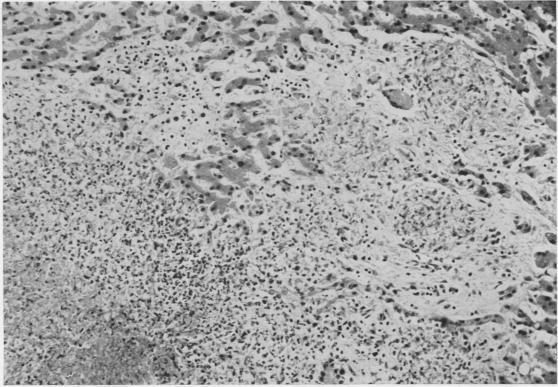

Non-reactive tuberculosis.

J Clin Pathol. 1954 Aug;7(3):216-25. doi: 10.1136/jcp.7.3.216.